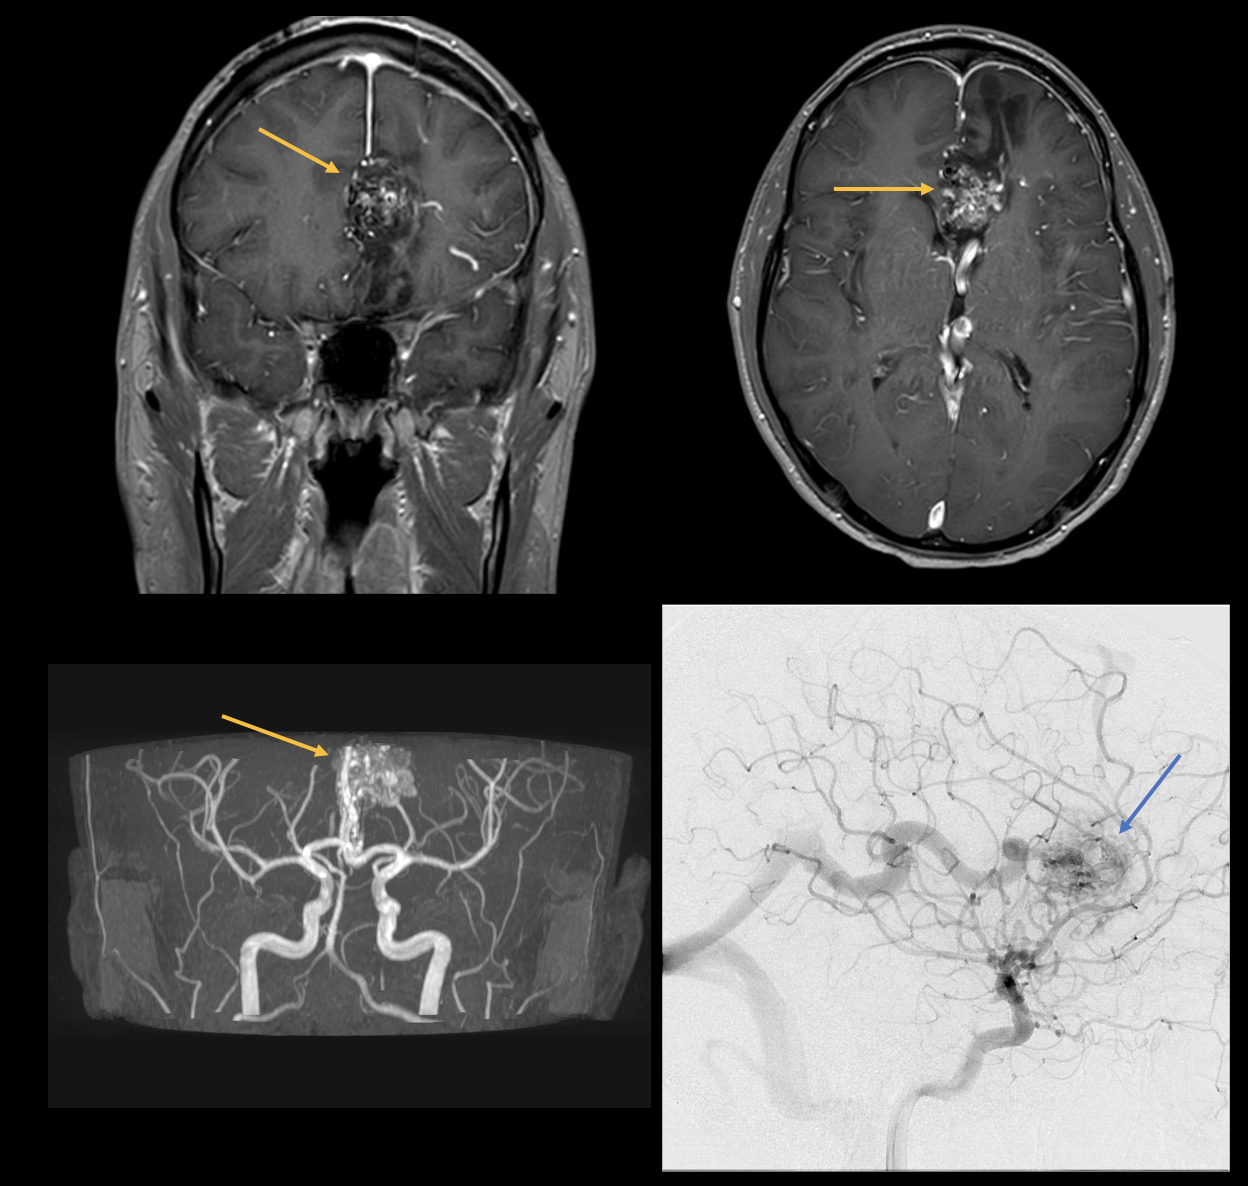

Mal di testa

Il mal di testa è una delle sindromi dolorose più comuni con cui i medici si confrontano nella pratica clinica quotidiana. Si distingue tra cefalea primaria (ad esempio, emicrania) e secondaria (ad esempio, dopo un trauma cranio-cerebrale o causata da infezioni). Le immagini seguenti mostrano un paziente ricoverato in ospedale con una forte cefalea e nausea. La risonanza magnetica e l'angiografia mostrano una malformazione arterovenosa (MAV). Una MAV è una malformazione vascolare congenita con connessioni shunt (nidus) tra arterie e vene cerebrali senza un letto capillare intermedio. Le malformazioni artero-venose possono rimanere asintomatiche per tutta la vita. Tuttavia, spesso si manifestano con cefalee tra i 20 e i 40 anni. Le emorragie intracraniche si verificano in circa il 50-60% dei pazienti, le crisi epilettiche e i deficit neurologici focali in circa il 25% delle persone colpite. La terapia classica è la resezione chirurgica, anche se il trattamento endovascolare è sempre più utilizzato.

image4.png

Figura 4: Immagini di risonanza magnetica assiale e coronale e angiografia a sottrazione digitale che mostrano le connessioni dello shunt tra arterie e vene. Il nidus è contrassegnato dai pilastri.